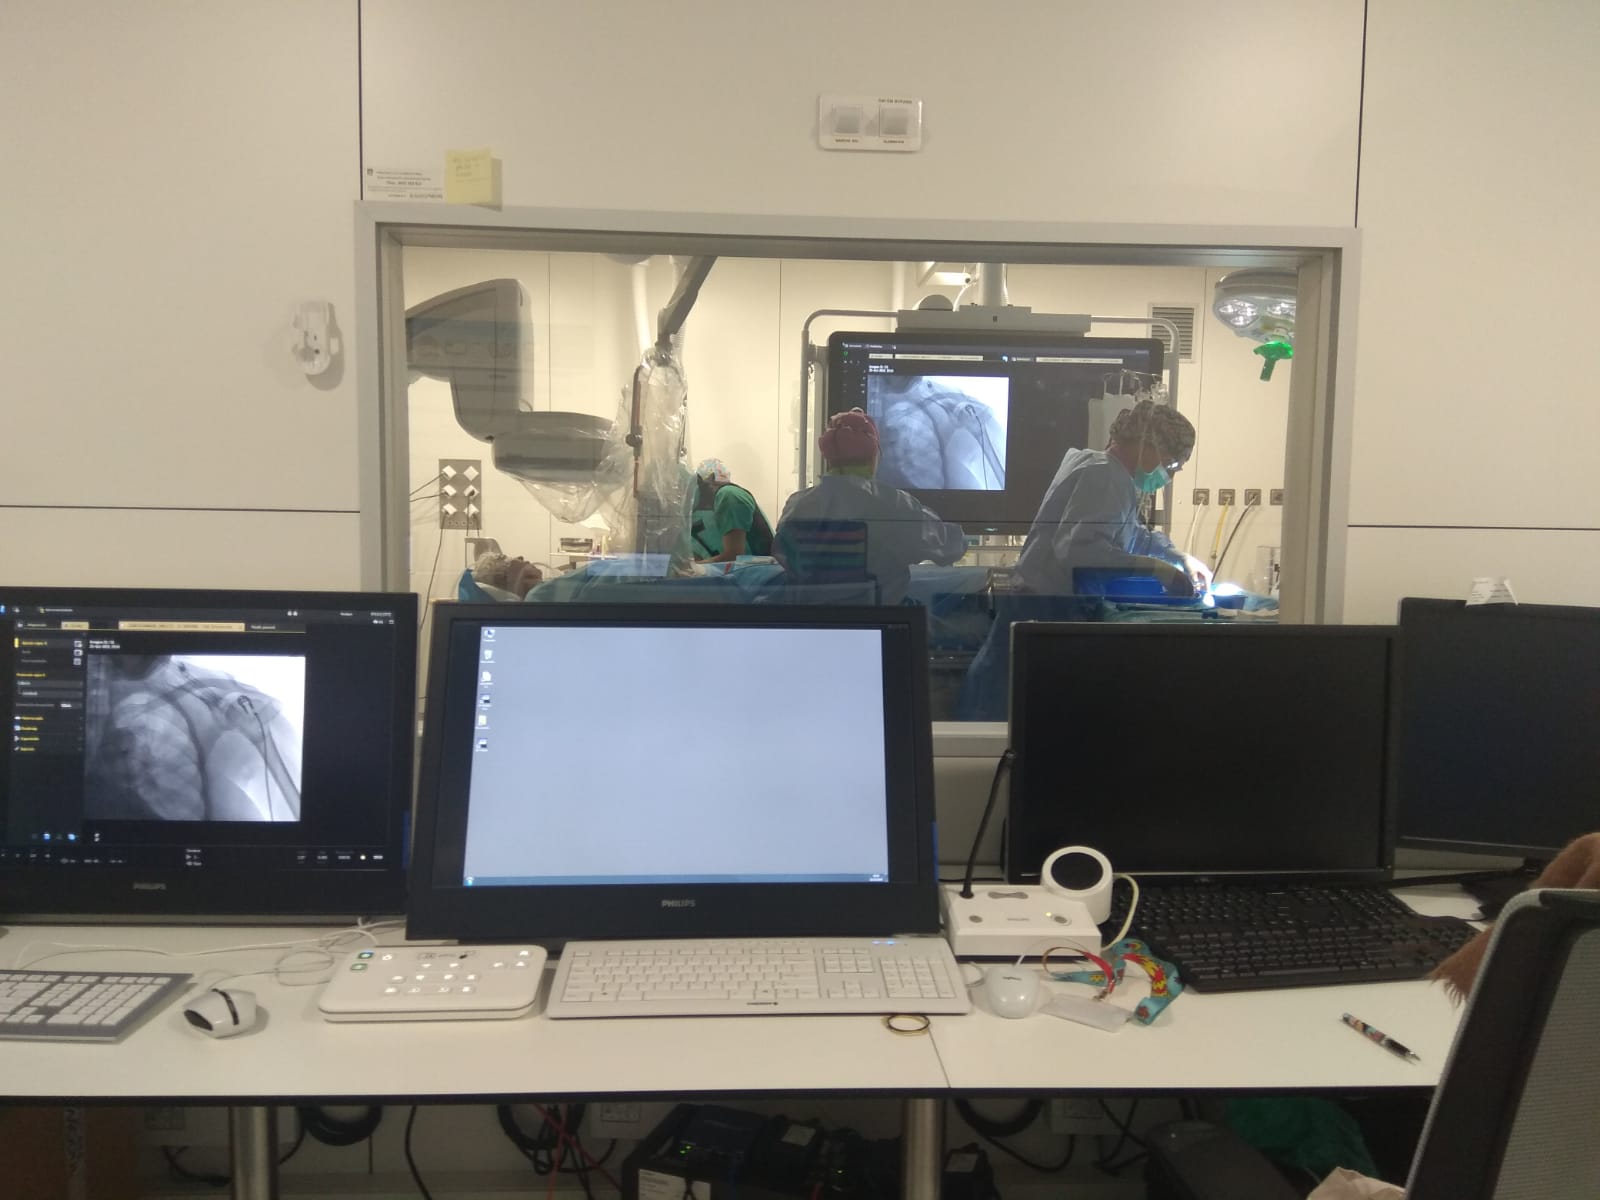

Aquests procediments es fan en una sala equipada amb tecnologia específica: la sala de radiologia intervencionista. Des del 3 d’octubre de 2018, dia en què es va atendre el primer cas al Trueta, que era també el primer pacient tractat amb teràpia endovascular fora de la demarcació de Barcelona, han entrat a la sala de radiologia intervencionista un total de 41 pacients, dels quals a 37 se’ls ha fet una trombectomia mecànica. En el 86 % dels casos s’ha aconseguit una recanalització arterial i s’ha pogut extreure el trombe que ocloïa el vas. El 29 de setembre passat es va estrenar el nou horari del servei, 12 hores diàries de dilluns a divendres, cosa que converteix el Trueta en l’Hospital de fora de l’àrea metropolitana de Barcelona amb un horari de cobertura més gran.

La sala de radiologia intervencionista durant la realització d'una trombectomia mecànica a un pacient que havia patit un ictus isquèmic.